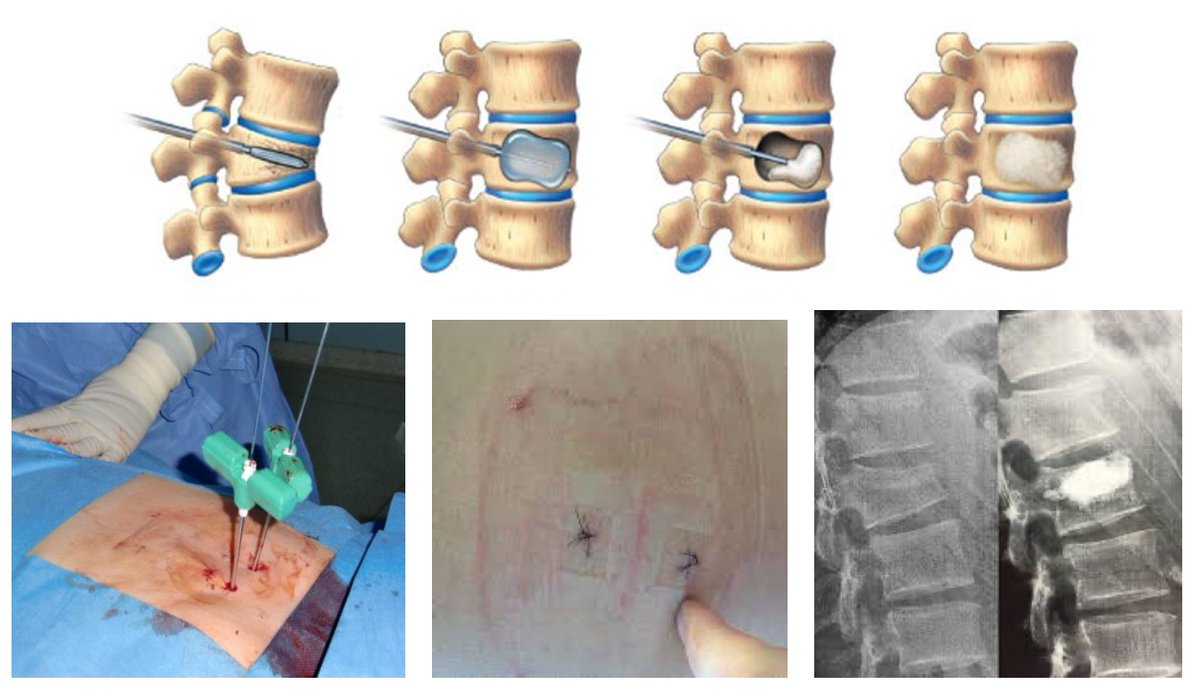

1⃣6⃣Lumbar interbody fusion for discopathy تغيير غضاريف الفقرات القطنية

تجرى عمليات تغيير الغضروف للفقرات القطنية للمرضى الذين يعانون من الآلام مزمنة في أسفل الظهر بسبب التهاب الغضروف المزمن. سابقًا تعمل هذه العمليات من الخلف من خلال جرح كبير ولكن هناك طرق حديثة تحافظ على الأنسجة

1⃣7⃣ المحيطة وتمكن من اجراء العملية من خلال جروح جانبية صغيرة. بل هناك طرق أحدث لتغيير الديسك إما عن طريق الأمام أو من الجنب أظهرت نتائج جداً فعالة من حيث سرعة زوال الآلام وتصحيح انحرافات العمود الفقري وتحدبه.

1⃣8⃣في بعض الأحيان تكون هناك حاجة لتثبيت الفقرات مع تغيير الغضروف حتى تعطي هذه التقنية الجراحية نتائج ممتازة....